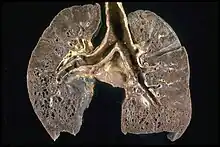

肺部病變是迄今為止最常見的結節病病理改變。約90%的患者在他們的患病過程中會出現胸部X線異常。總體而言,約50%患者出現長期的肺部異常,5%至15%有肺實質進行性纖維化。肺結節病主要是肺間質的炎性改變,涉及到肺泡、小支氣管和小血管。通常在急性和亞急性的情況下體檢會聽到肺部的幹性啰音。[20]

許多情況下,結節病會造成肺部的病變,包括肺容量的減少,順應性(肺泡伸展的能力)的下降。因此,異常的胸部X線表現,往往是結節病的首要發現。人們往往通過胸部X線來做出初步診斷或者評估肺部病變的嚴重程度。

中華人民共和國的醫學資料中將胸部X線的改變分為五期,以Ⅰ期和Ⅱ期較為常見:[58]

- 0 期:肺部X線檢查陰性,肺部清晰無明顯的病變。

- Ⅰ期:兩側肺門和/或縱隔淋巴結腫大,右主支氣管旁淋巴結常常伴有腫大,而肺內無明顯異常。

- Ⅱ期:肺門淋巴結的腫大,伴肺浸潤影。

- Ⅲ期:可見肺部浸潤影,並無肺門淋巴結腫大。

- Ⅳ期:肺內發生纖維化、肺大皰和肺囊腫等改變。

以上分類僅僅是相對而言的,並不能說明一定會有0期-Ⅳ期的病變,可以是跳躍式發展。CT掃描(尤其是HRCT)能夠更準確地估計結節病的類型、肺間質的病變程度與淋巴結的腫大情況。[58]